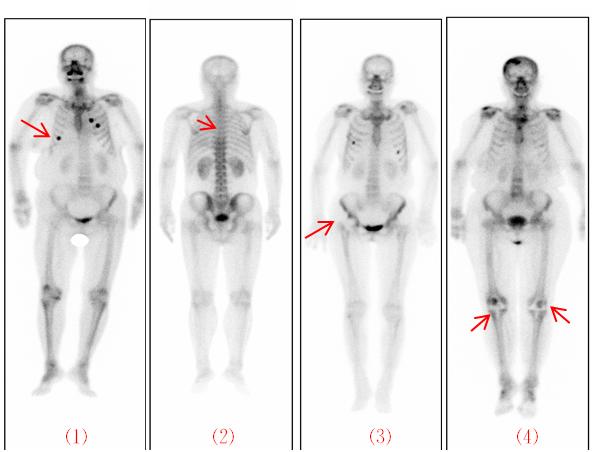

骨掃描圖像是顯像設(shè)備接受骨骼發(fā)射出來的射線形成的,外部金屬物品(如紐扣、項(xiàng)鏈、硬幣、鑰匙、皮帶金屬扣環(huán)、手機(jī)、手鐲等)、玉飾、寶石、膏藥、暖貼、護(hù)腰帶等會(huì)阻擋射線,其所在部位在圖像上表現(xiàn)為“冷區(qū)”,即偏白的影像,會(huì)影響診斷,建議穿著寬松、棉質(zhì)、無飾物衣物前來檢查。體內(nèi)有無法取出金屬植入物(如起搏器、輸液港、假肢、假牙、血管支架、鋼釘、內(nèi)固定物等),仍然可以接受骨顯像檢查,不過,需要您將相關(guān)情況告知工作人員,以利于正確診斷。

6、掃描時(shí),保持全身不動(dòng)

掃描時(shí)需躺平,保持全身不動(dòng)約20分鐘。如掃描時(shí)有肢體移位,會(huì)出現(xiàn)重影、體位不對(duì)稱,有可能造成兩側(cè)放射性分布不對(duì)稱,影響圖像質(zhì)量。